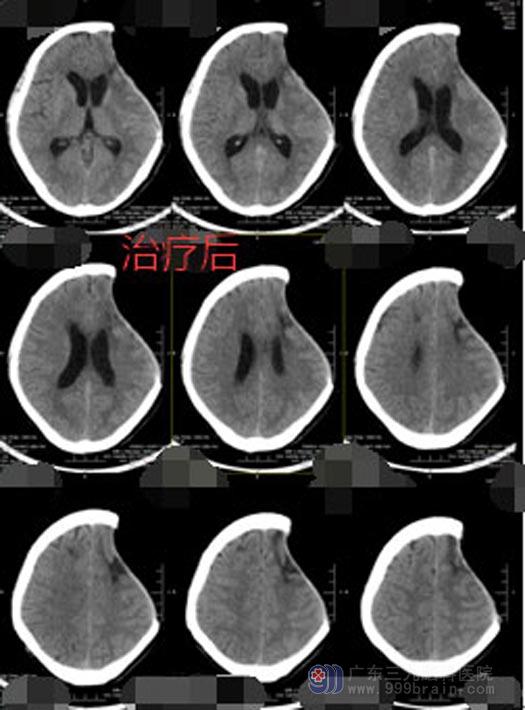

广东三九脑科医院副院长、神经外五科主任鲁明详细了解患者病情、仔细查体后认为病人是有好转希望的。头颅CT检查显示脑水肿,入院当日立即行“左额颞血肿清除术+内减压术”,术后病人身体较弱,送ICU 监护,患者痰多,又持续高热,胸部CT提示肺部感染严重,进行抗感染的同时给予纤支镜治疗,经过多日的精心护理,陈大哥总算睁着眼睛从ICU出来了。虽然对外界仍没有反应,但是总算看到了希望。继续进行高压氧、针灸、推拿等康复促醒治疗后,陈大哥终于清醒了过来。

▲治疗后CT